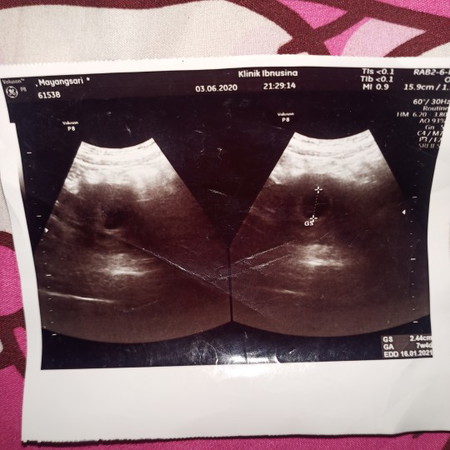

Ngapain ke dokter kalo nanyanya disini? Emang pas periksa diem"an bun sama dokternya?? Itu hamil 7minggu 4hari, dan hanya kelihatan kantungnya aja, janinnya belum keliatan.

Emang gakdijelasinyah bun ? dokter periksa gak ngobrol gitu apa diem2 aja ? kita jdi pasien juga kudu banyak tanya . Itu masih kantong kalau ngeliat tulisan gs nya belum terlihat janinnya . Kalau ada janin ada tulisan CRL

Kalau dokternya tidak aktip, kita yang harus bertanya aktip bun biar kita udah pulang gak banyak pertanyaan di pikiran kita😁itu baru kelihatan kantung kehamilan nya saja